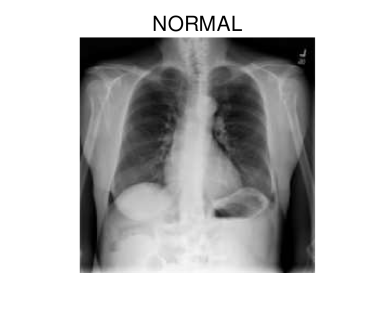

In hospitals, chest X-rays can mitigate these drawbacks by enabling a fast and reliable diagnosis. Figure 1 shows chest X-ray scans of healthy (top) and COVID-19 (bottom) patients in direct comparison. Even though patchy consolidations are recognizable in the COVID-19 scans, such X-rays remain challenging to interpret. Specialists, however, are able to identify the severity of a case early on and can take measures without waiting for lab results.